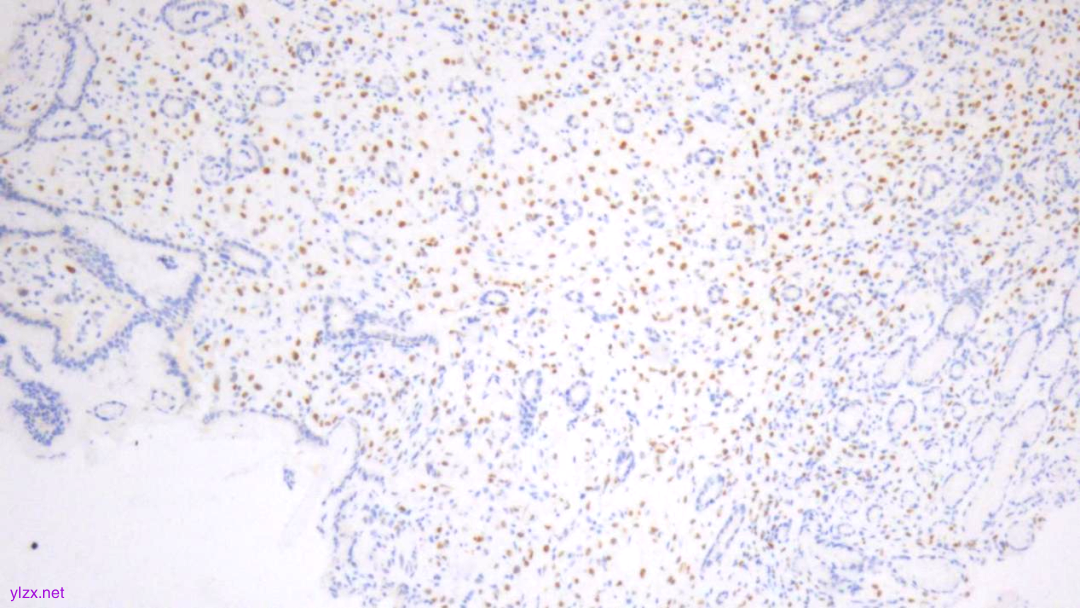

Ki-67(散在+)

ki-67(个别细胞+)